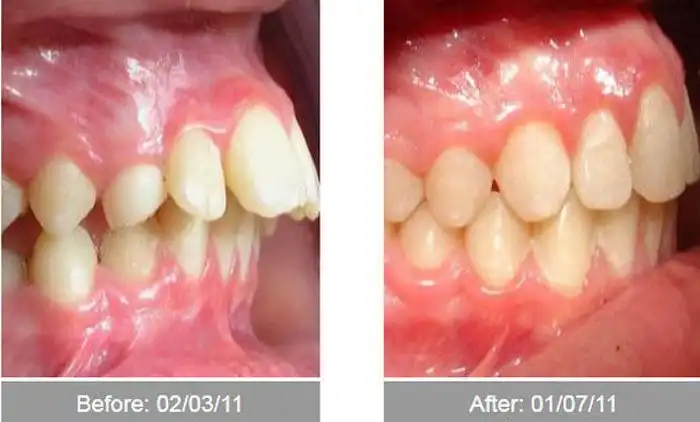

Эти сравнительные снимки в очередной раз доказывают,

что при желании можно серьезно изменить свой внешний вид,

причем, как в лучшую сторону, так и в худшую ;)